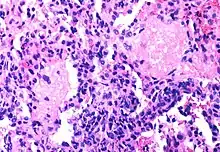

Only a small number of CD4+ T-cells are infected by HIV, not enough to damage the immune system

Although the fraction of CD4+ T-cells that is infected with HIV at any given time is never high (only a small subset of activated cells serve as ideal targets of infection), several groups have shown that rapid cycles of death of infected cells and infection of new target cells occur throughout the course of the disease.[39] Macrophages and other cell types are also infected with HIV and serve as reservoirs for the virus.

Furthermore, like other viruses, HIV is able to suppress the immune system by secreting proteins that interfere with it. For example, HIV's coat protein, gp120, sheds from viral particles and binds to the CD4 receptors of otherwise healthy T-cells; this interferes with the normal function of these signalling receptors. Another HIV protein, Tat, has been demonstrated to suppress T cell activity.

Infected lymphocytes express the Fas ligand, a cell-surface protein that triggers the death of neighboring uninfected T-cells expressing the Fas receptor.[40] This "bystander killing" effect shows that great harm can be caused to the immune system even with a limited number of infected cells.